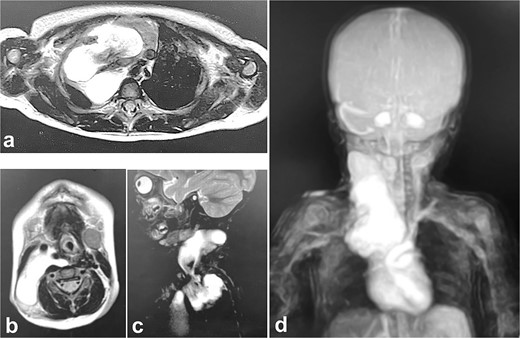

MRI at evaluation after 2 months of Kampo medicine administration. A huge right cervical mediastinal lymphangioma is recognized. (a) Horizontal section in mediastinal region, (b) horizontal section in cervical region, (c) sagittal section in cervical mediastinal region, (d) MRA.